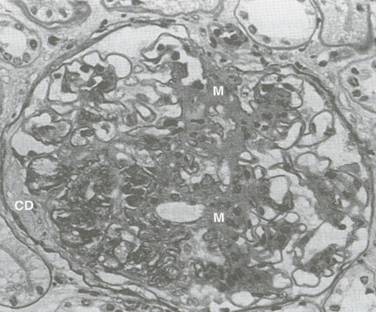

a). Leziunile nodulare - descrise de Kimmelstiel Wilson (Figura 5.10), au fost considerate

mult timp ca fiind caracteristice nefropatiei diabetice. Mecanismele de formare a acestor noduli nu sunt elucidate. Se incrimineaza atat procesele de mezangioliza focala [117] cat si cele de necroza fibrinoida [32]. Se caracterizeaza prin aparitia de noduli hialini acelulari, cu aspect fibrilar. Nodulii sunt bine demarcati, eozinofili, localizati in regiunile centrale ale lobulilor glomerulari. Ei sunt frecvent incercuiti de celule spumoase. Sunt relativ omogeni la coloratia cu hematoxilina si au o structura laminata dupa coloratia cu acid-Schiff periodic. Caracteristicile acestui tip de leziuni sunt: neregularitatea marimii si distributiei in si intre glomeruli si localizarea lor departe de hil. Probabil locul lor de origine este mezangiul. Distrugerea mezangiala si liza centrului lobular este corelata cu dilatarea capilara microanevrismala, urmata de reorganizarea laminara a ramasitelor mezangiale. Formarea nodulilor este inalt specifica pentru glomerulopatia diabetica, dar alte boli renale, cum ar fi glomerulonefrita mezangiocapilara, nefropatia amiloida, boala lanturilor usoare s.a., pot fi asociate cu anormalitati nodulare. Microscopia electronica si studiile in imunofluorescenta aduc elemente distincte in nefropatia diabetica [96]. Este general acceptat ca nodulii nu sunt prezenti in absenta leziunilor difuze si apar numai dupa o lunga perioada de boala (aproximativ 14 ani). Nodulii Kimmelstiel Wilson nu sunt totdeauna prezenti in nefropatia diabetica. Prevalenta lor variaza considerabil, intre 12 - 55%.

Figura 5.10. Glomeruloscleroza nodulara (Kimmelstiel Wilson)